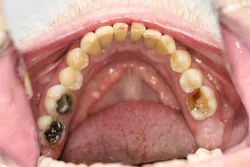

Upon receiving approval from his oncologist to commence with dental care three months later, his examination revealed the following (figures 1-5):

- Severe class III active periodontal disease

- Rampant, generalized cervical caries with some lesions quite extensive in nature

- Broken no. 8 (chief complaint)

- Broken/carious nos. 18, 19, and 30; caries on no. 2

- Generalized dry mouth with white patchy mucosa; he did have a complaint of having a “sticky mouth.” Note: When we took the photos, we had to put water in his mouth because it was so dry.

The genesis for his caries was evident–drug-induced dry mouth and time were the perfect storm for widespread infection that demanded immediate management. Suffice to say, my news to the patient was not welcome.